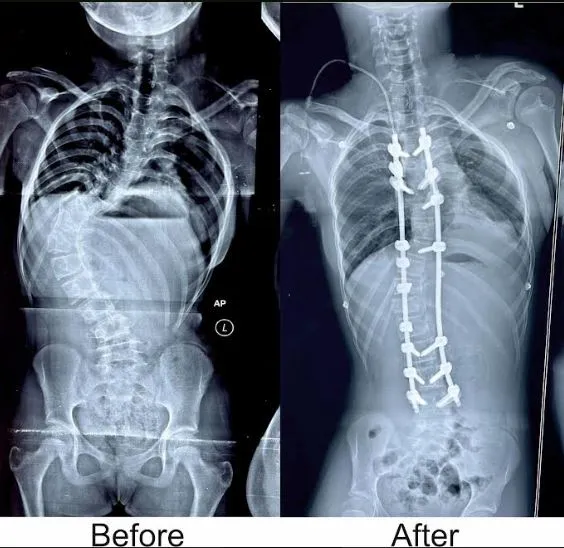

डॉ. राउत ने बताया कि लड़की की रीढ़ की हड्डी 'एस' आकार की हो गई थी, जिससे भविष्य में उसके लिए और अधिक समस्याएं पैदा कर सकती थी। किम्स में कुशल डॉक्टरों, उन्नत तकनीक और उपकरणों की उपलब्धता के कारण रीढ़ की हड्डी की ऐसी दुर्लभ सर्जरी संभव हुई। मरीज अब पूरी तरह से ठीक है। डॉ. राउत ने कहा कि कुछ दिनों के आराम के बाद वह सामान्य जीवन जी सकती है।

गौरतलब है कि ओडिशा के किसी निजी अस्पताल में पहली बार रीढ़ की हड्डी की इतनी जटिल सर्जरी की गई है। इस सर्जरी में आमतौर पर सात-आठ घंटे लगते हैं, लेकिन डॉ. राउत और उनकी मेडिकल टीम इसे महज 4 घंटे में अंजाम देने में सफल रही।